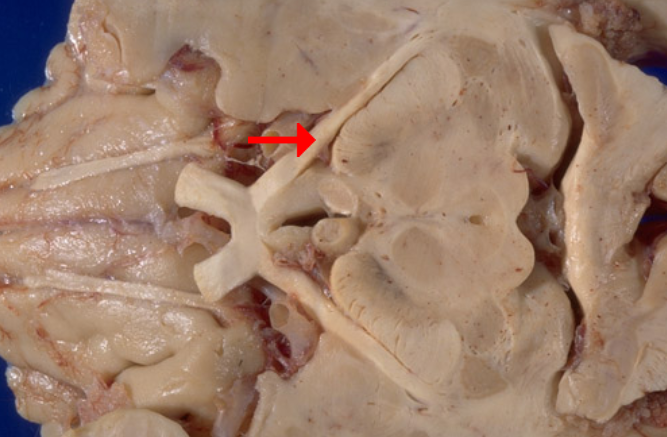

Label this cranial nerve

Olfactory (CN I) nerve

Label this cranial nerve

Optic (CN II) nerve

Label this cranial nerve

Oculomotor (CN III) nerve

Label this cranial nerve

Trochlear (CN IV) nerve

Label this cranial nerve

Trigeminal (CN V) nerve

Label this cranial nerve

Abducens (CN VI) nerve

Label this cranial nerve

Facial (CN VII) nerve

Label this cranial nerve

Vestibulocochlear (VIII) nerve

Label this cranial nerve

Glossopharyngeal (CN IX) nerve

Label this cranial nerve

Vagus (CN X) nerve

Label this cranial nerve

Accessory (CN XI) nerve

Label this cranial nerve

Hypoglossal (CN XII) nerve